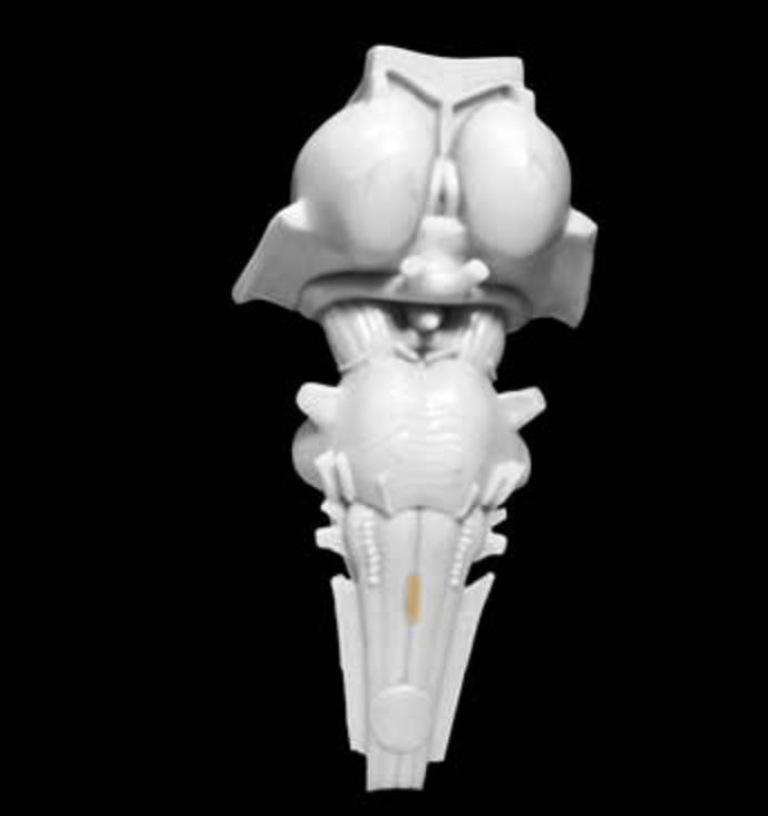

Cerebral peduncles

Three major white matter structures that contain efferent and afferent axons of the cerebellum (peduncle means stalk). These three peduncles are named the inferior, middle, and superior cerebellar peduncles.

Cerebellum

Prominent convoluted hindbrain structure (Latin for "little brain") consisting of a three-layered cortex, subcortical white matter, deep nuclei, and three peduncles that connect the cerebellum and brainstem. The cerebellum is concerned with the coordination of ongoing movement, motor planning, and motor learning; it also plays a role in coordinating and sequencing cognitive processing.

Cerebellar peduncles (superior, middle, inferior)

Three major white matter structures that contain efferent and afferent axons of the cerebellum (peduncle means stalk). These three peduncles are named the inferior, middle, and superior cerebellar peduncles. Prominent structures (peduncle means "stalk") observed on the ventral surface of the midbrain comprising the tegmentum and the more ventrally located white matter tracts (basis pedunculi). In common usage, the term cerebral peduncle denotes these white matter tracts, which contain the efferent axons of the cerebral cortex that project to the brainstem and spinal cord.

Red nucleus

Prominent nucleus located in the tegmentum of the rostral midbrain. Its major parvocellular (small-celled) division conveys signals from the cerebral cortex to the inferior olivary nucleus, which in turn modulates activity in the cerebellum. A minor magnocellular (large-celled) division may contribute to the control of the distal upper extremities via projections to the lateral ventral horn of the spinal cord, projections that form the rubrospinal tract; however, this projection is vestigial and variable in humans and its functional significance is uncertain.

Superior colliculus

Paired hillocks on the dorsal surface of the midbrain overlying the cerebral aqueduct, which are involved in orienting movements of the head and eyes. Together with the inferior colliculi, these structures are also known as the "tectum" (which means roof) and the "quadrageminal bodies".

Tectum

Structure in the dorsal midbrain that forms a roof over the cerebral aqueduct (tectum means roof); comprises the superior and inferior colliculi (also called the "quadrageminal bodies").